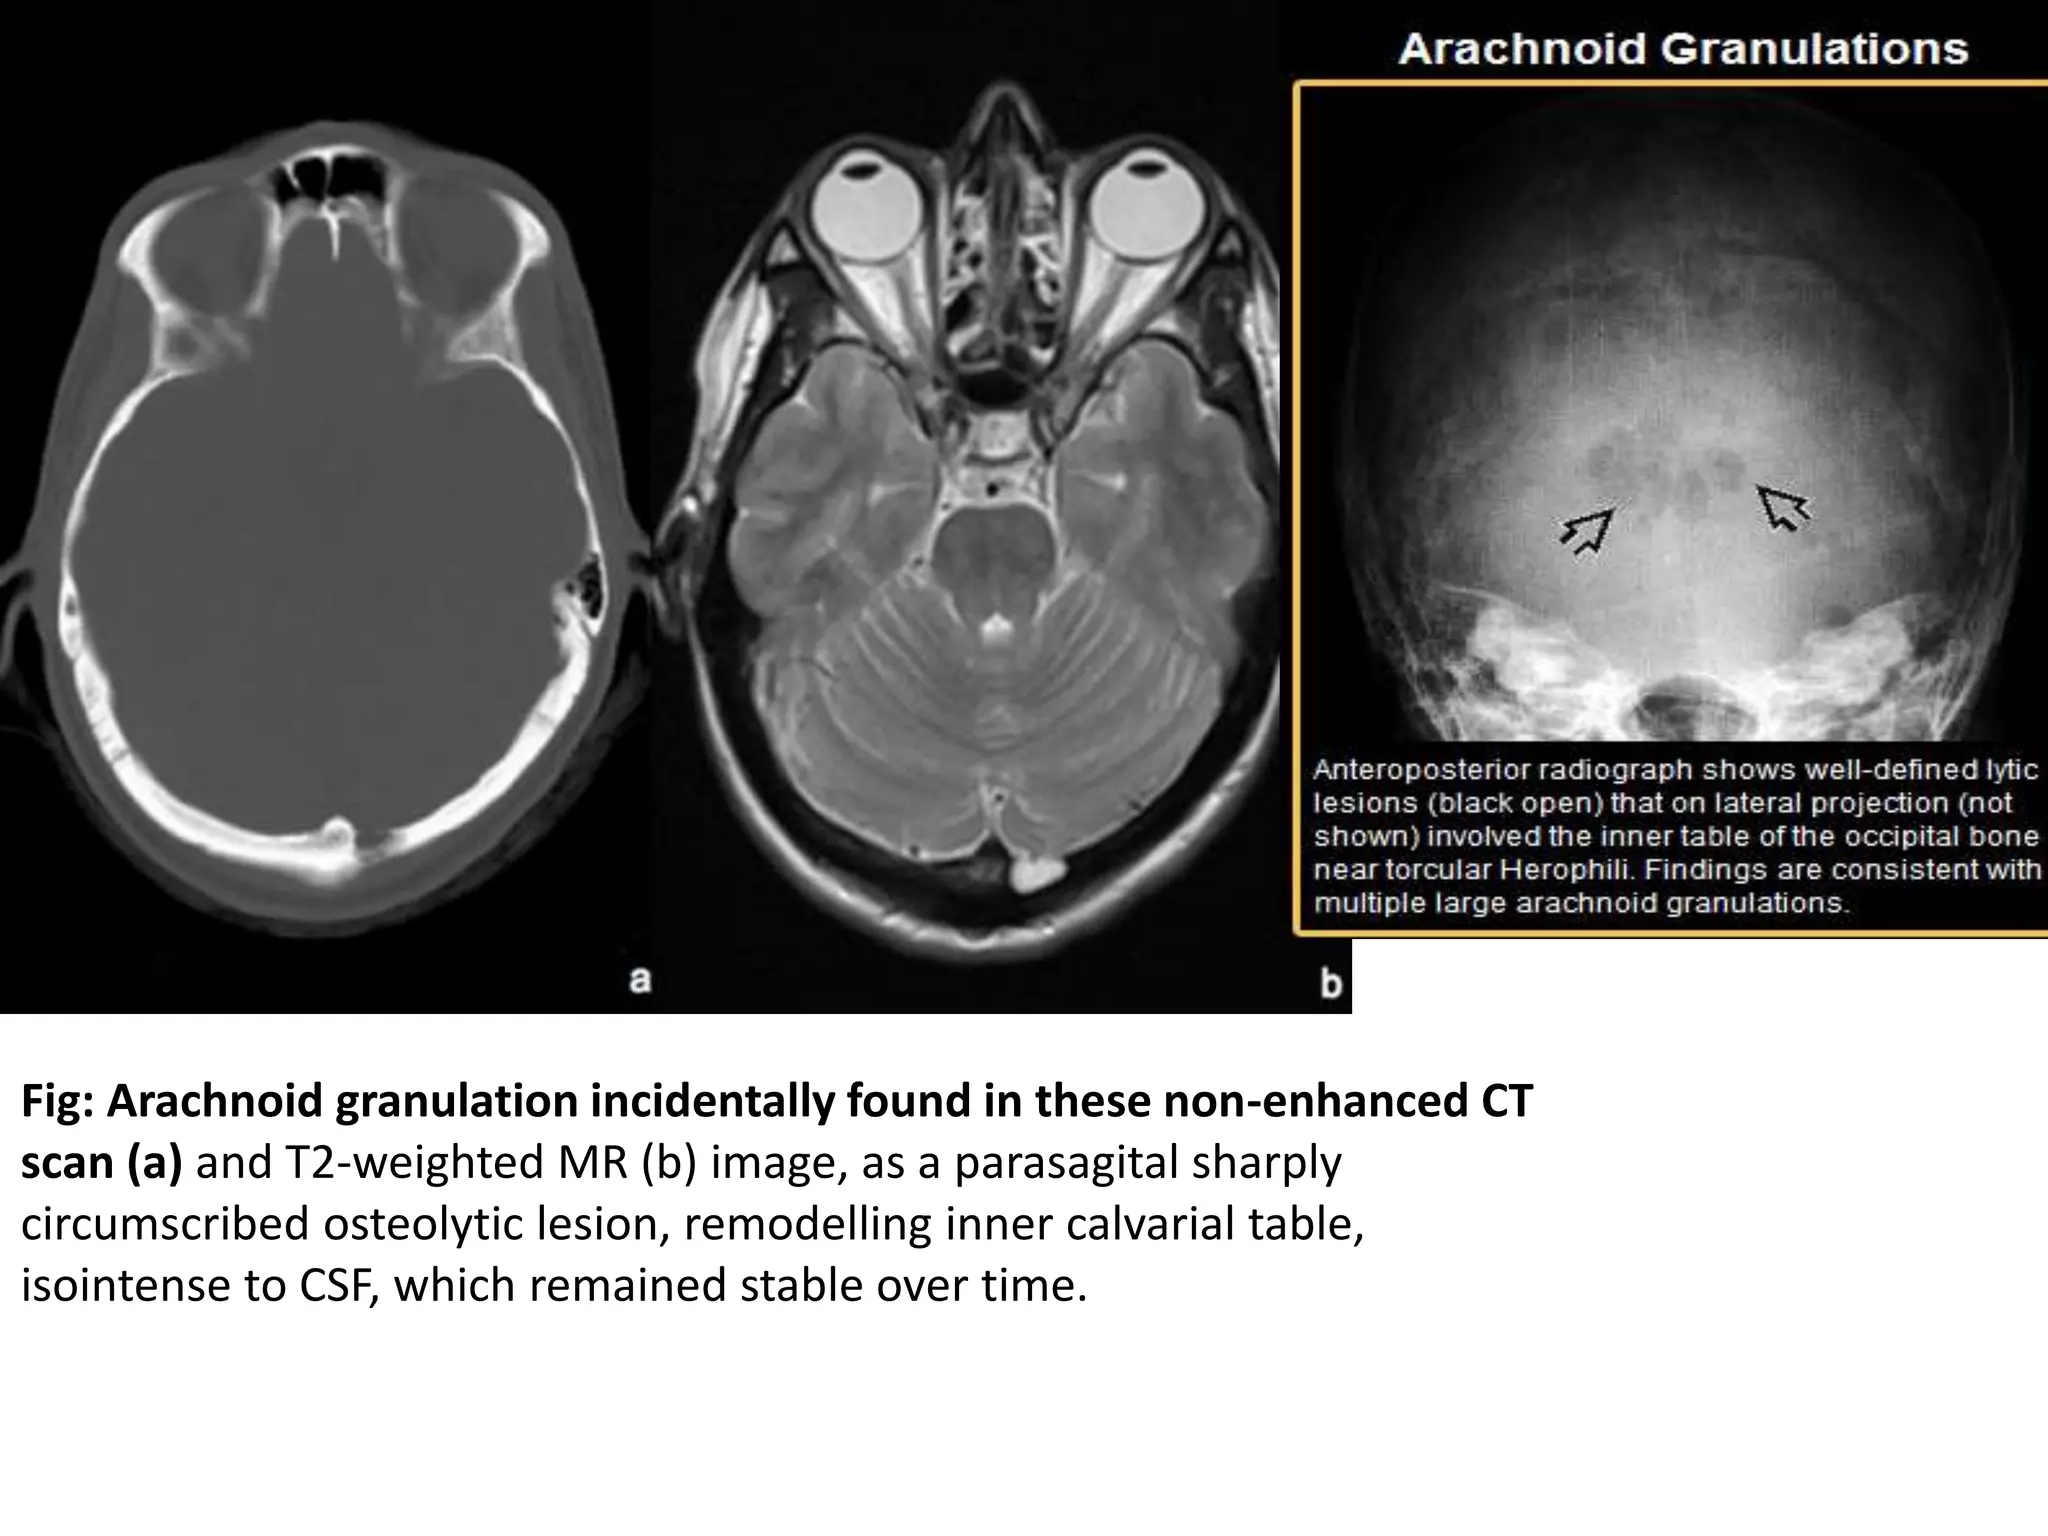

Arachnoid Granulations

• also known as Pacchionian granulations.

• are normal anatomical structures visible in approximately

1% of patients corresponding to enlarged arachnoid villi

that are involved in the filtration of CSF from the

subarachnoid space to the venous system.

• Hypertrophic arachnoid granulations as a result of high

CSF pressure may be responsible for lytic skull lesions.

• Most are located close to the superior sagittal sinus.

• Appear as rounded and sharply circumscribed lucencies

with sclerotic border, seen on MR as projections within the

sinus of signal intensity similar to that of CSF and on MR

angiography as filling defects

Fig: Arachnoid granulation incidentally found in these non-enhanced CT

scan (a) and T2-weighted MR (b) image, as a parasagital sharply

circumscribed osteolytic lesion, remodelling inner calvarial table,

isointense to CSF, which remained stable over time.

Fig: Arachnoid granulationincidentally found in these non-enhanced CT scan (a) and T2-weighted MR (b) image, as a parasagital sharply circumscribed osteolytic lesion, remodelling inner calvarial table, isointense to CSF, which remained stable over time.